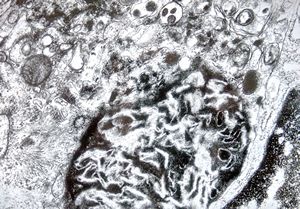

Whipple disease